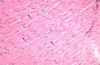

dense regular CT

Structure :Densely packed collagen fibers are parallel to direction of stress Function: Provides great strength and flexibility primarily in a single direction Location: Tendons and ligaments

Structure :Densely packed collagen fibers are parallel to direction of stress Function: Provides great strength and flexibility primarily in a single direction Location: Tendons and ligaments

dense regular CT